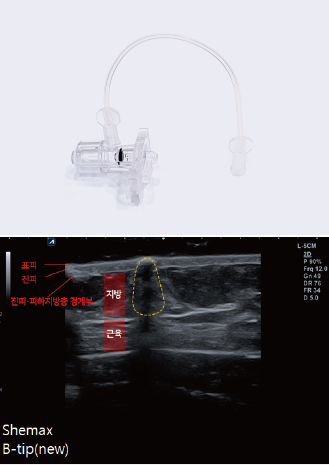

Transcutaneous Pneumatic InjectionSHEMAX uses compressed air pressure to spray liquid medicine instantaneously.

At this time, liquid medicine is delivered to a certain depth through physical energy.

Face nozzle and body nozzle

Face nozzles and body nozzles are distinguished into different types

to help select a suitable one according to the treatment location.